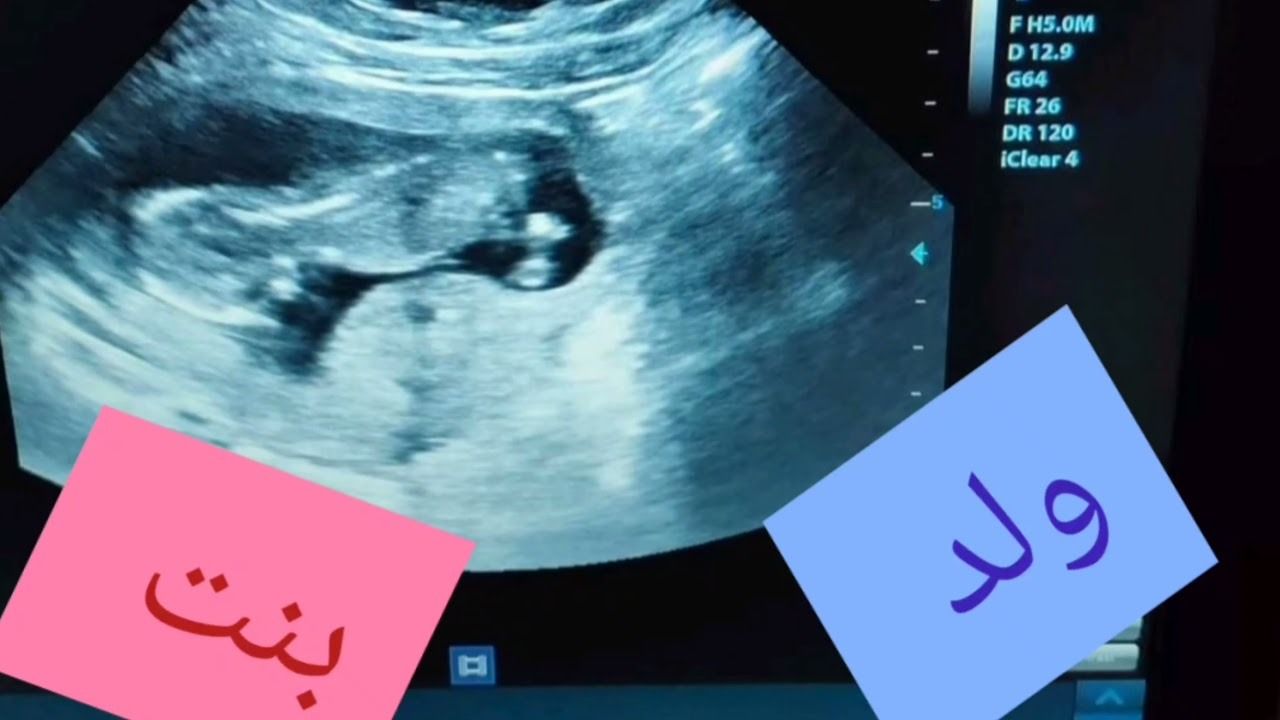

وقد ظهر جهاز حديث يسمى السونار للكشف عن عمر الحمل وحالة الجنين وجنسه، يستخدم جهاز السونار لإنشاء صورة ثنائية الأبعاد على شاشة الكمبيوتر، يستمر حوالى عشرين دقيقة، ويعطي معلومات عن عمر الحمل وتقييم الجنين، يقيس هذا الاختبار حركة تدفق الدم والسرعة التي ينتقل فيها الدم في الرحم أو الحبل السري أو في قلب الجنين أو حول جسمه، سنتعرف في هذا المقال عن الوقت الذي يمكننا فيه معرفة جنس الجنين، وهل يخطئ السونار في تحديد نوع الجنين في الأسبوع 12.

هل يخطئ السونار في تحديد نوع الجنين في الأسبوع 12؟

رغم اشتهار السونار بأمانه على الجنين، وباستطاعته الكبيرة على تحديد نوع الجنين، إلا أن الآراء تختلف في هذا الخصوص، وسنعرض بعض الآراء في ما يخص سؤال هل يخطئ السونار في تحديد جنس الجنين في الأسبوع 12:

- أكد بعض استشاريين النساء والتوليد أن نسبة الخطأ في تحديد نوع الجنين بالسونار ضئيلة جدًا لا تتجاوز 2% وذلك في الأسبوع 18 حتى الأسبوع 20، أما قبل هذا الوقت فتزيد نسبة الخطأ.

- كما أكدوا أن السونار يكشف جنس الجنين بالبحث عن بعض العلامات، وباستخدام الموجات فوق الصوتية.

- أوضح بعض أطباء النساء والتوليد أن هناك بعض العوامل التي تؤثر سلبًا في تحديد نوع الجنين بالسونار، وذلك عند سؤالهم هل يخطئ السونار في تحديد نوع الجنين في الأسبوع 12 ومن أبرز هذه العوامل:

- إجراء السونار مبكرًا، فبالسؤال هل يخطئ السونار في تحديد نوع الجنين في الأسبوع 12 وضح أطباء الحمل والولادة أنه ينصح بإجراء السونار بعد الأسبوع الثامن عشر لضمان الحصول على نتائج دقيقة.

- وقد طرح الكثير من الأسئلة فيما يتعلق بدقة السونار منها هل يخطئ السونار في تحديد نوع الجنين في الأسبوع 12، وكانت معظم آراء الاستشاريين والأطباء بأنه لا يفضل أبدًا أن تخضع المرأة لفحص السونار من أجل تحديد جنس الجنين في الأسبوع 12 من الحمل، حيث تكون نسبة الخطأ مرتفعة.